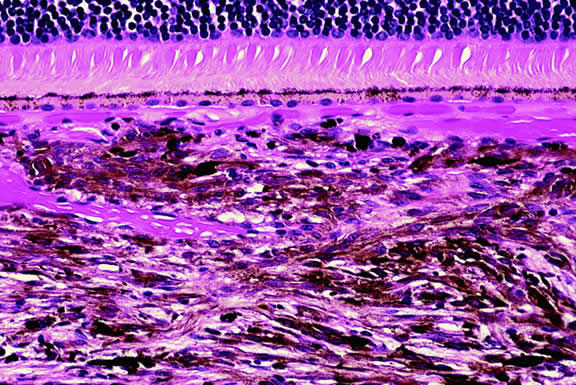

Lymphoma

Although non-Hodgkin's lymphoma often affects the orbit and conjunctiva, intraocular involvement by lymphoma is relatively rare and occurs in two basic ways. First, patients who have widely disseminated systemic lymphoma may develop secondary ocular involvement whose typical manifestation is uveal infiltration. Second, in the variant of central nervous system (CNS) lymphoma that has been called primary lymphoma of the CNS and retina, the vitreous characteristically is involved and the uvea is spared. The latter entity also has been called vitreous large cell lymphoma or ocular “reticulum cell sarcoma.”205–208 In addition to the vitreous, the lymphoma cells also infiltrate the retina, and typically collect between Bruch's membrane and the retinal pigment epithelium, forming solid yellowish RPE detachments, which are highly suggestive of the diagnosis. This rare variant of primary CNS lymphoma should be suspected in older patients who have chronic vitritis that is unresponsive to therapy. Cytologic examination of diagnostic vitrectomy specimens reveals a highly cellular and extensively necrotic infiltrate that contains atypical lymphocytes with prominent nucleoli and protrusions of the nuclear membrane (Fig. 53). The significance of elevated vitreous interleukin 10 levels as a diagnostic marker for lymphoma is controversial.209,210

Fig. 53. Primary central nervous system lymphoma, vitreous. Diagnostic vitrectomy specimen contains large atypical lymphocytes, necrotic lymphoid cells, and nuclear debris. Lymphoma cells in inset have nuclear membrane protrusions and prominent nucleoli. Main figure, Millipore filter. (Hematoxylin-eosin, × 250.)